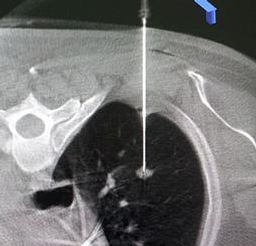

Cryoablation